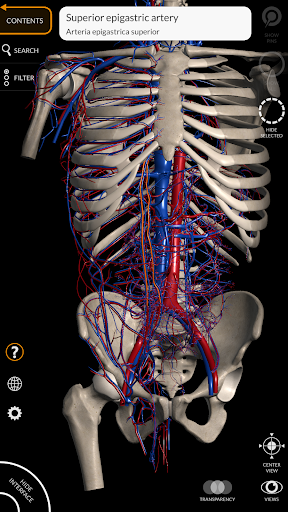

"Anatomy 3D Atlas" vous permet d'étudier l'anatomie humaine de manière simple et interactive.

Grâce à une interface simple et intuitive, il est possible d'observer chaque structure anatomique sous n'importe quel angle.

Les modèles anatomiques 3D sont particulièrement détaillés et avec des textures jusqu'à une résolution de 4k.

La subdivision par régions et les vues prédéfinies facilitent l'observation et l'étude de parties individuelles ou de groupes de systèmes et les relations entre différents organes.

MODÈLES ANATOMIQUES 3D

• Système cardiovasculaire

• Faites pivoter et zoomez chaque modèle dans l'espace 3D

• Option pour masquer ou isoler un ou plusieurs modèles sélectionnés

• Filtrez pour masquer ou afficher chaque système

• Fonction de transparence